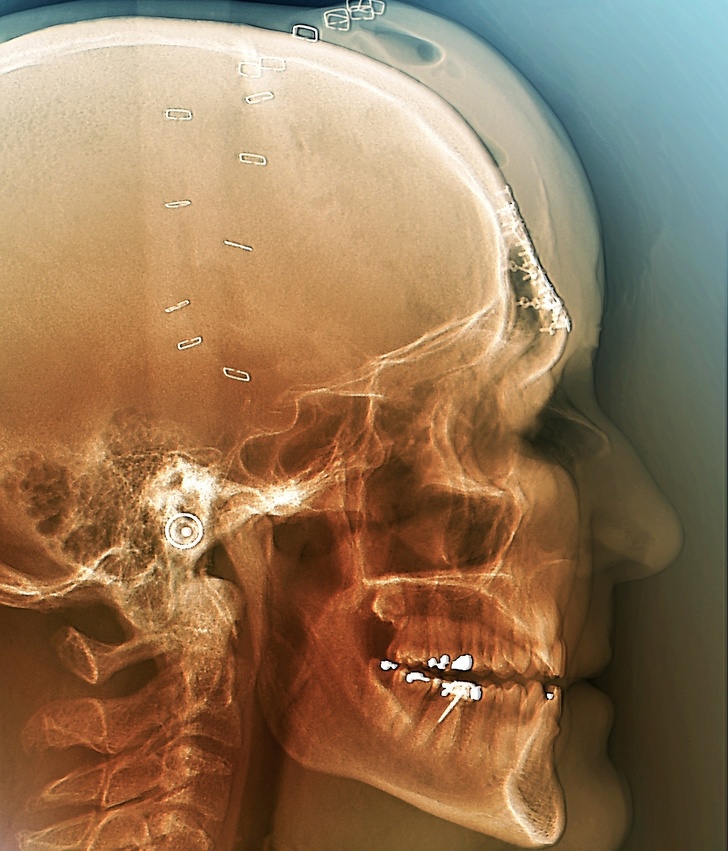

15. Знімок, зроблений після операції по відновленню черепа людини, постраждалої в ДТП